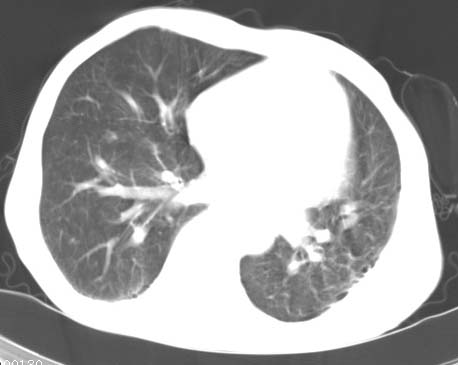

标题: CT14816:男性81岁 胸痛 咳嗽2月 2周前提示右下肺感染. [打印本页]

标题: CT14816:男性81岁 胸痛 咳嗽2月 2周前提示右下肺感染.

男性病人 81岁 胸痛 咳嗽2月 2周前提示右下肺感染.

今片ct示双肺多发结节影 可以这样诊断吗?1\双肺感染性病变 结核待排.

2\双肺纤维硬结灶,左肺肺气肿.

3\肺间质纤维化,胸膜肥厚粘连.

1:右肺外周多发小结节病灶,考虑转移性子瘤.

2;右上肺及左肺纤维结核灶,并斑痕性肺气肿.

3:慢支炎并肺气肿.伴胸膜肥厚钙化.

1:右肺外周多发小结节病灶,考虑转移性子瘤.因患者年龄较大,双肺多发结节在肺外带,转移性子瘤不能除外

此病人,诊断如下:1、双肺陈旧结核,活动与否请结合临床及其它检查。2、慢支炎,肺气肿,并双肺

多发肺大泡。3,胸膜肥厚、粘连。4、右下肺多个小结节,转移瘤不能除外。

病人桶状胸,胸廓肌肉消瘦;两上肺均可见纤维条索灶,下肺外围胸膜下可见间质纤维化改变,右下肺沿肺纹理分部结节样病灶,边缘光滑,考虑1、慢支并局灶性间质纤维化、右下肺合并感染,2、两上肺为陈旧性肺结核灶并瘢痕旁型肺气肿3、右下肺转移瘤待排。

两肺上叶见多发索条状高密度影,右肺下叶见片状、结节状高密度影,两肺体积增大,胸膜下区见囊状低密度影、内有分隔结构。左肺下叶见网格影。两侧胸膜见增厚影。诊断:两肺继发性肺结核。慢性支气管炎合并感染。肺气肿。肺间质纤维化。胸膜增厚。